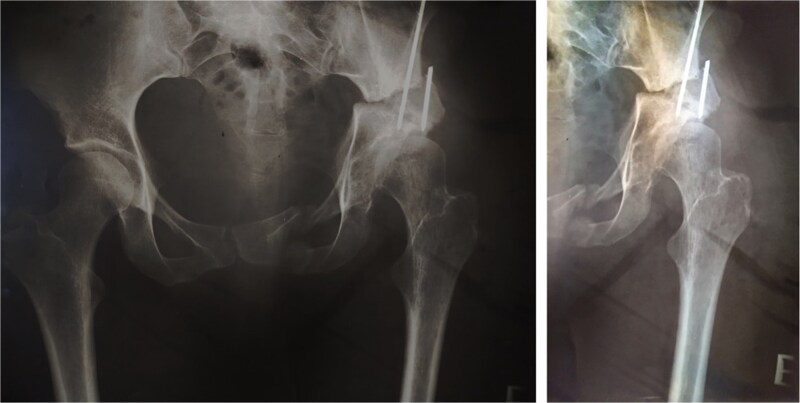

一位35岁的女性髋臼发育不良患者接受了Pol Le Cœur三重骨盆截骨术(TPO)。28年后,她出现疼痛的终末期髋关节骨关节炎,并接受了全髋关节置换术(THA)。植入加压式无骨水泥髋臼杯和骨水泥直股柄,无并发症。在13年的随访中,髋关节x线片显示没有假体不稳定和假体松动的迹象。TPO可能不能完全预防髋关节骨关节炎的进展。本例患者在截骨术后28年出现进行性终末期骨关节炎,需要THA。Pol Le Cœur对于患有低度骨关节炎的年轻成人,TPO是一种治疗症状性髋臼发育不良的可行选择,可有效延缓髋关节假体植入。TPO后混合THA在中期随访中能获得非常满意的临床和影像学结果。

A 35-year-old female patient with acetabular dysplasia underwent a Pol Le Cœur triple pelvic osteotomy (TPO). Twenty-eight years later, she presented with painful end-stage hip osteoarthritis and underwent total hip arthroplasty (THA). A press-fit cementless acetabular cup and a cemented straight femoral stem were implanted without complications. At 13-year follow-up, hip radiographs revealed no signs of prothesis instability and no signs of implant loosening. TPO may not completely prevent the progression of hip osteoarthritis. In this case, the patient developed progressive end-stage osteoarthritis 28 years after the osteotomy, requiring THA. Pol Le Cœur TPO is a viable treatment option for symptomatic acetabular dysplasia in younger adults with low-grade osteoarthritis, effectively delaying hip prosthesis implantation. Hybrid THA after TPO can yield very satisfactory clinical and radiographic outcomes at mid-term follow-up.